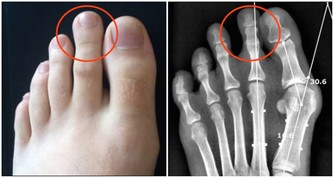

4.其他

凡是兩年不長粉刺的,(吃大量辣椒都不長的);平時老到點不餓的;腳蘚突然不癢的;皮膚老是覺的熱而體溫不高的;皮膚變緊但卻沒彈性的;每天下午低熱的;赤脈貫瞳的,臉變的發青的或黑的都要小心了。最好早查,查不出來也要好好養著,因為腫瘤小時查不出來。當然不一定都是癌,小心養著就好了,身體可是自個的!